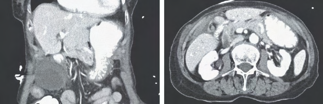

Recent studies indicate that Generative Pre-trained Transformer 4 with Vision (GPT-4V) outperforms human physicians in medical challenge tasks. However, these evaluations primarily focused on the accuracy of multi-choice questions alone. Our study extends the current scope by conducting a comprehensive analysis of GPT-4V's rationales of image comprehension, recall of medical knowledge, and step-by-step multimodal reasoning when solving New England Journal of Medicine (NEJM) Image Challenges - an imaging quiz designed to test the knowledge and diagnostic capabilities of medical professionals. Evaluation results confirmed that GPT-4V outperforms human physicians regarding multi-choice accuracy (88.0% vs. 77.0%, p=0.034). GPT-4V also performs well in cases where physicians incorrectly answer, with over 80% accuracy. However, we discovered that GPT-4V frequently presents flawed rationales in cases where it makes the correct final choices (27.3%), most prominent in image comprehension (21.6%). Regardless of GPT-4V's high accuracy in multi-choice questions, our findings emphasize the necessity for further in-depth evaluations of its rationales before integrating such models into clinical workflows.